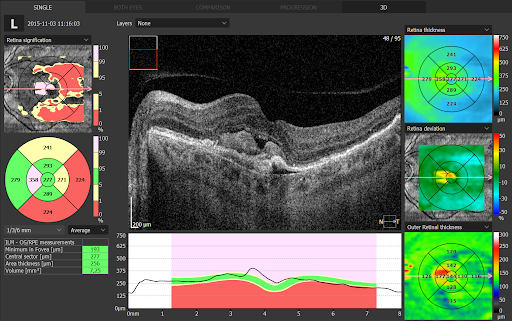

H φασματική οπτική τομογραφία συνοχής (S -OCT) αποτελεί τη νεότερη μέθοδο απεικόνισης της ωχράς κηλίδας και του οπτικού νεύρου. Πρόκειται για μια εξέταση αιχμής με την οποία πραγματοποιείται λεπτομερέστατη χαρτογράφηση όλων των δομών του οφθαλμού. Επιτρέπει τη λήψη τομών πολύ υψηλής ανάλυσης και αντίθετα με την αξονική τομογραφία που χρησιμοποιείται για τη λήψη τομών στα άλλα μέρη του σώματος, η Οπτική τομογραφία συνοχής δε χρησιμοποιεί επιβλαβή ακτινοβολία αλλά μια μονοχρωματική δέσμη φωτός (laser).

Το OCT είναι πλέον απαραίτητο για τη διάγνωση αλλά και την παρακολούθηση της θεραπευτικής πορείας πλήθους παθήσεων του αμφιβληστροειδούς, όπως η ηλικιακή εκφύλιση της ωχράς κηλίδας, το οίδημα της ωχράς κηλίδας σε έδαφος διαβητικής αμφιβληστροειδοπάθειας ή φλεβικών αποφράξεων, η κεντρική ορώδης χοριοαμφιβληστροειδοπάθεια, η οπή ωχράς κηλίδας, η επαμφιβληστροειδική μεμβράνη, οι υαλοειδο-ωχρικές έλξεις κ.α.

Το OCT έχει επίσης σημαντική θέση στη διάγνωση και παρακολούθηση του γλαυκώματος. Επιτρέπει τη μελέτη του πάχους του οπτικού νεύρου και των νευρικών ινών, την πρώιμη διάγνωση του γλαυκώματος (πριν δημιουργηθούν διαταραχές στα οπτικά πεδία) και την καταγραφή μεταβολών στην πορεία της νόσου.